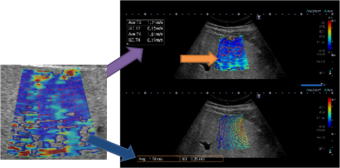

到达时间参数成像(P-MFI):

1. 对于具有不同血供特点的疾病方便的实施鉴别诊断。

2.对造影剂的灌注按时间顺序彩色编码,清晰显示微血管造影剂灌注。